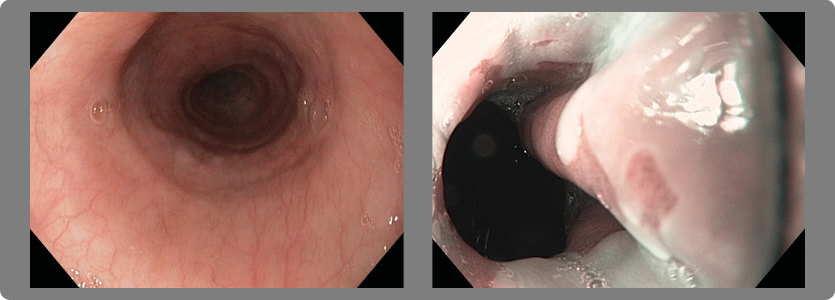

3- Esófago de Barrett

Es una condición en la cual la mucosa del esófago distal, que normalmente está cubierta de epitelio escamoso, cambia a epitelio columnar como consecuencia del RGE y puede evolucionar hasta un cáncer muy maligno.

4- Cáncer del esófago

Es una condición en la cual el RGE produjo un esófago de Barrett o una estrechez péptica que evolucionó a cáncer; esta es una enfermedad muy maligna con una sobrevida no mayor al 15% de los enfermos.